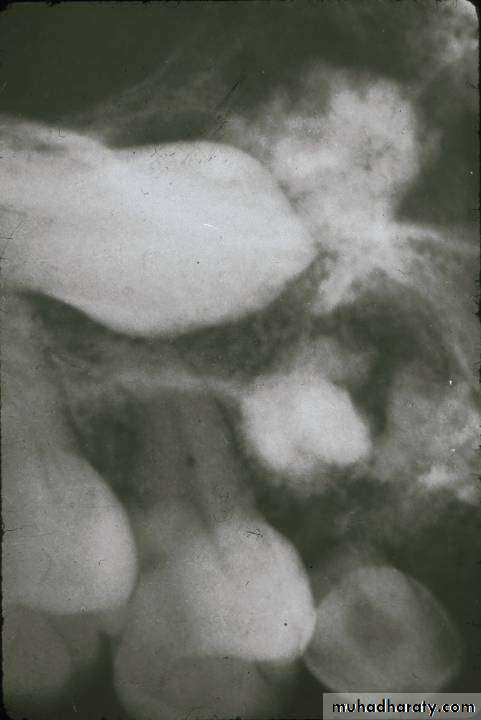

• Copyright 2003, Elsevier Science (USA). All rights reserved.• Odontomas

• Odontomas are developmental malformation ( hamartoma) of dental tissue, it is not neoplasim• 1. Compound: Composed of

• 2. Complex: composed of a conglomerate mass of enamel and dentin, which bears no anatomic resemblance to a tooth

• Compound

• Complex

• Compound Complex

• The compound type shows apparent tooth shapes while the complex type appears as uniform opaque mass with no apparent tooth shapes present• Copyright 2003, Elsevier Science (USA). All rights reserved.

• Histopathology:• The compound odontoma is composed of enamel, dentin and cementum arrange in recognizable tooth forms; some enamel matrix may be retained in immature and hypomineralized specimens.

• The complex odontoma is composed of enamel, dentin and cementum but these tissues are arranged in a random manner that bears no morphological resemblance to a tooth.